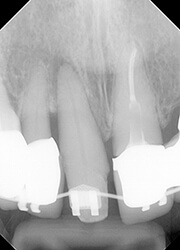

【治療中】

とりあえずは抜髄せず、生活歯のまま、ヒビの最深部が歯周ポケット内に現れてくるまで、部分矯正で挺出を試みました。

4mmほど挺出させたところで腫れが消失して、歯髄も生活歯のままであることが確認できました。

一度挺出を始めると早いもので、数週間で部分矯正は終了です。